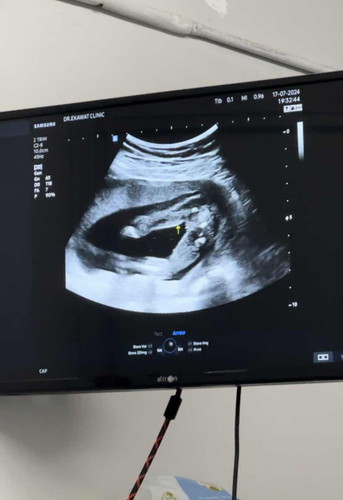

รบกวนแม่ๆช่วยดูให้หน่อยค่ะ อายุครรภ์ 18 วีค คุณหมอบอกได้ลูกสาว100% แต่แม่ดูไม่ออกค่ะ กลัวน้องเปลี่ยนเพศ😂